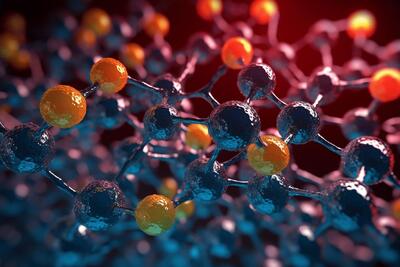

مکمل استیل ال کارنیتین یک مولکول متشکل از اسید استیک و آمینواسید ال کارنیتین است و به طور طبیعی در مغز انسان یافت می شود.

این ساختار سه بعدی مولکولهای درمانی را پس از سکته به مغز میرساند.

چای جو سرشار از آنتیاکسیدانهایی است که میتوانند از بدن در برابر رادیکالهای آزاد محافظت کنند. رادیکالهای آزاد مولکولهای مضری هستند که تجمع آنها در بدن عملکرد سلولها را مختل میکند و منجر به بروز التهاب و بیماریهای خطرناک مانند سرطان میشود.

هنگامیکه این ماده در معرض طول موج خاصی از نور قرار می گیرد، مولکول ها آرایش خود را تغییر می دهند و در نتیجه رنگ ماده تغییر می کند.

محققان کشف داروی دانشگاه موناش دریافتند که یک مولکول چربی طبیعی به نام